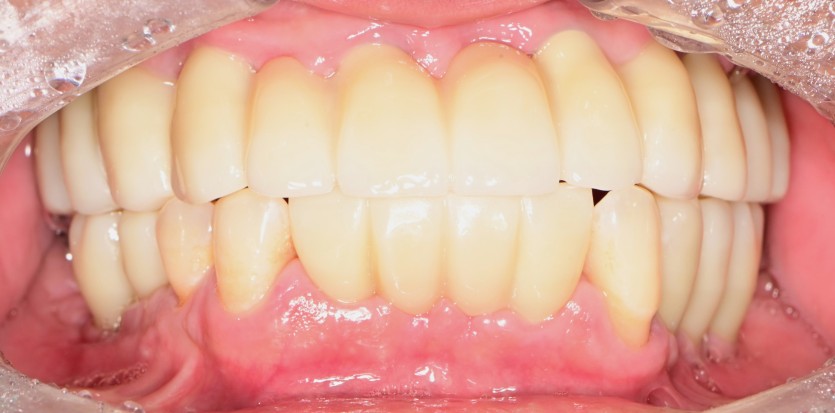

전체 임플란트 증례입니다.

17개의 임플란트로 완성하였습니다